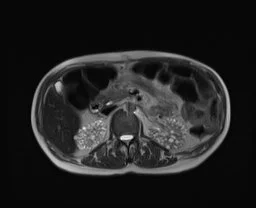

Hypertrophy of Column of Bertin

• Refers to enlarged piece of renal cortex that protrudes through the medulla

• Commonly mistaken for a renal mass

• Isoechoic/Isointense/Isodense to renal cortex

• Will show communication with the regular peripheral renal cortex

• Usually unilateral and on the left